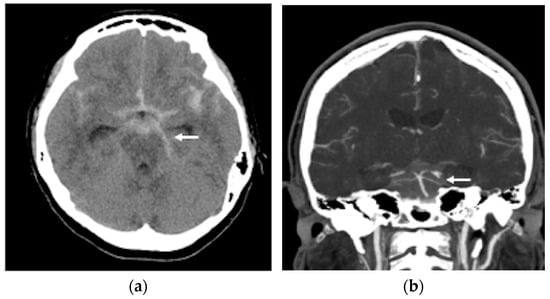

A non-contrast brain computed tomography (CT) scan revealed diffuse subarachnoid hemorrhage (SAH) with a thickness exceeding 1 mm within the basal cistern, predominantly along the left side ambient cistern (Figure 1a). Subsequent CT angiography (CTA) was performed to investigate the etiology of the SAH and demonstrated an irregular vessel contour in the left PCA P2 segment, with a focal arterial pouch consistent with a dissecting aneurysm with a saccular rupture component (Figure 1b). Evaluation of the lumbar spine using CT (Figure 2a) and axial T2-weighted magnetic resonance imaging (MRI) (Figure 2b) revealed an L2 burst fracture with significant spinal canal compromise, resulting in approximately 65% dural sac stenosis. Digital subtraction catheter angiography (DSA) with 3D rotational angiographic acquisition was performed using the Siemens Artis Q angiography system with PURE technology (Siemens Healthineers, Forchheim, Germany). Image reconstruction and aneurysm morphometric quantitative measurements were performed on the Siemens syngo X-Workplace using the syngo 3D Angio (Dyna3D) module. The DSA identified an approximately 5 mm long fusiform dilation along the anterior portion of the left PCA P2 segment (Figure 3a, D1), accompanied by an inferiorly projecting saccular pouch measuring 2.5 mm in diameter (Figure 3a, D2). These findings were diagnostic of a ruptured dissecting aneurysm with a superimposed saccular aneurysm sac (Figure 3a). All cerebrovascular imaging examinations was performed by neuroradiologist Dr. Wu Ming-Ji. A second neuroradiologist Dr. Shen Chao-Yu independently reviewed the images and confirmed the morphometric measurements.

Figure 1.

(a) A non-contrast brain computer tomography (CT) revealed diffuse subarachnoid hemorrhage (SAH), with a thickness exceeding 1 mm within the basal cistern, predominantly along the left side ambient cistern (white arrow head); (b) brain CT angiography demonstrated an irregular vessel contour in the left PCA P2 segment, with a focal arterial pouch consistent with a dissecting aneurysm with a saccular rupture (white arrow head).